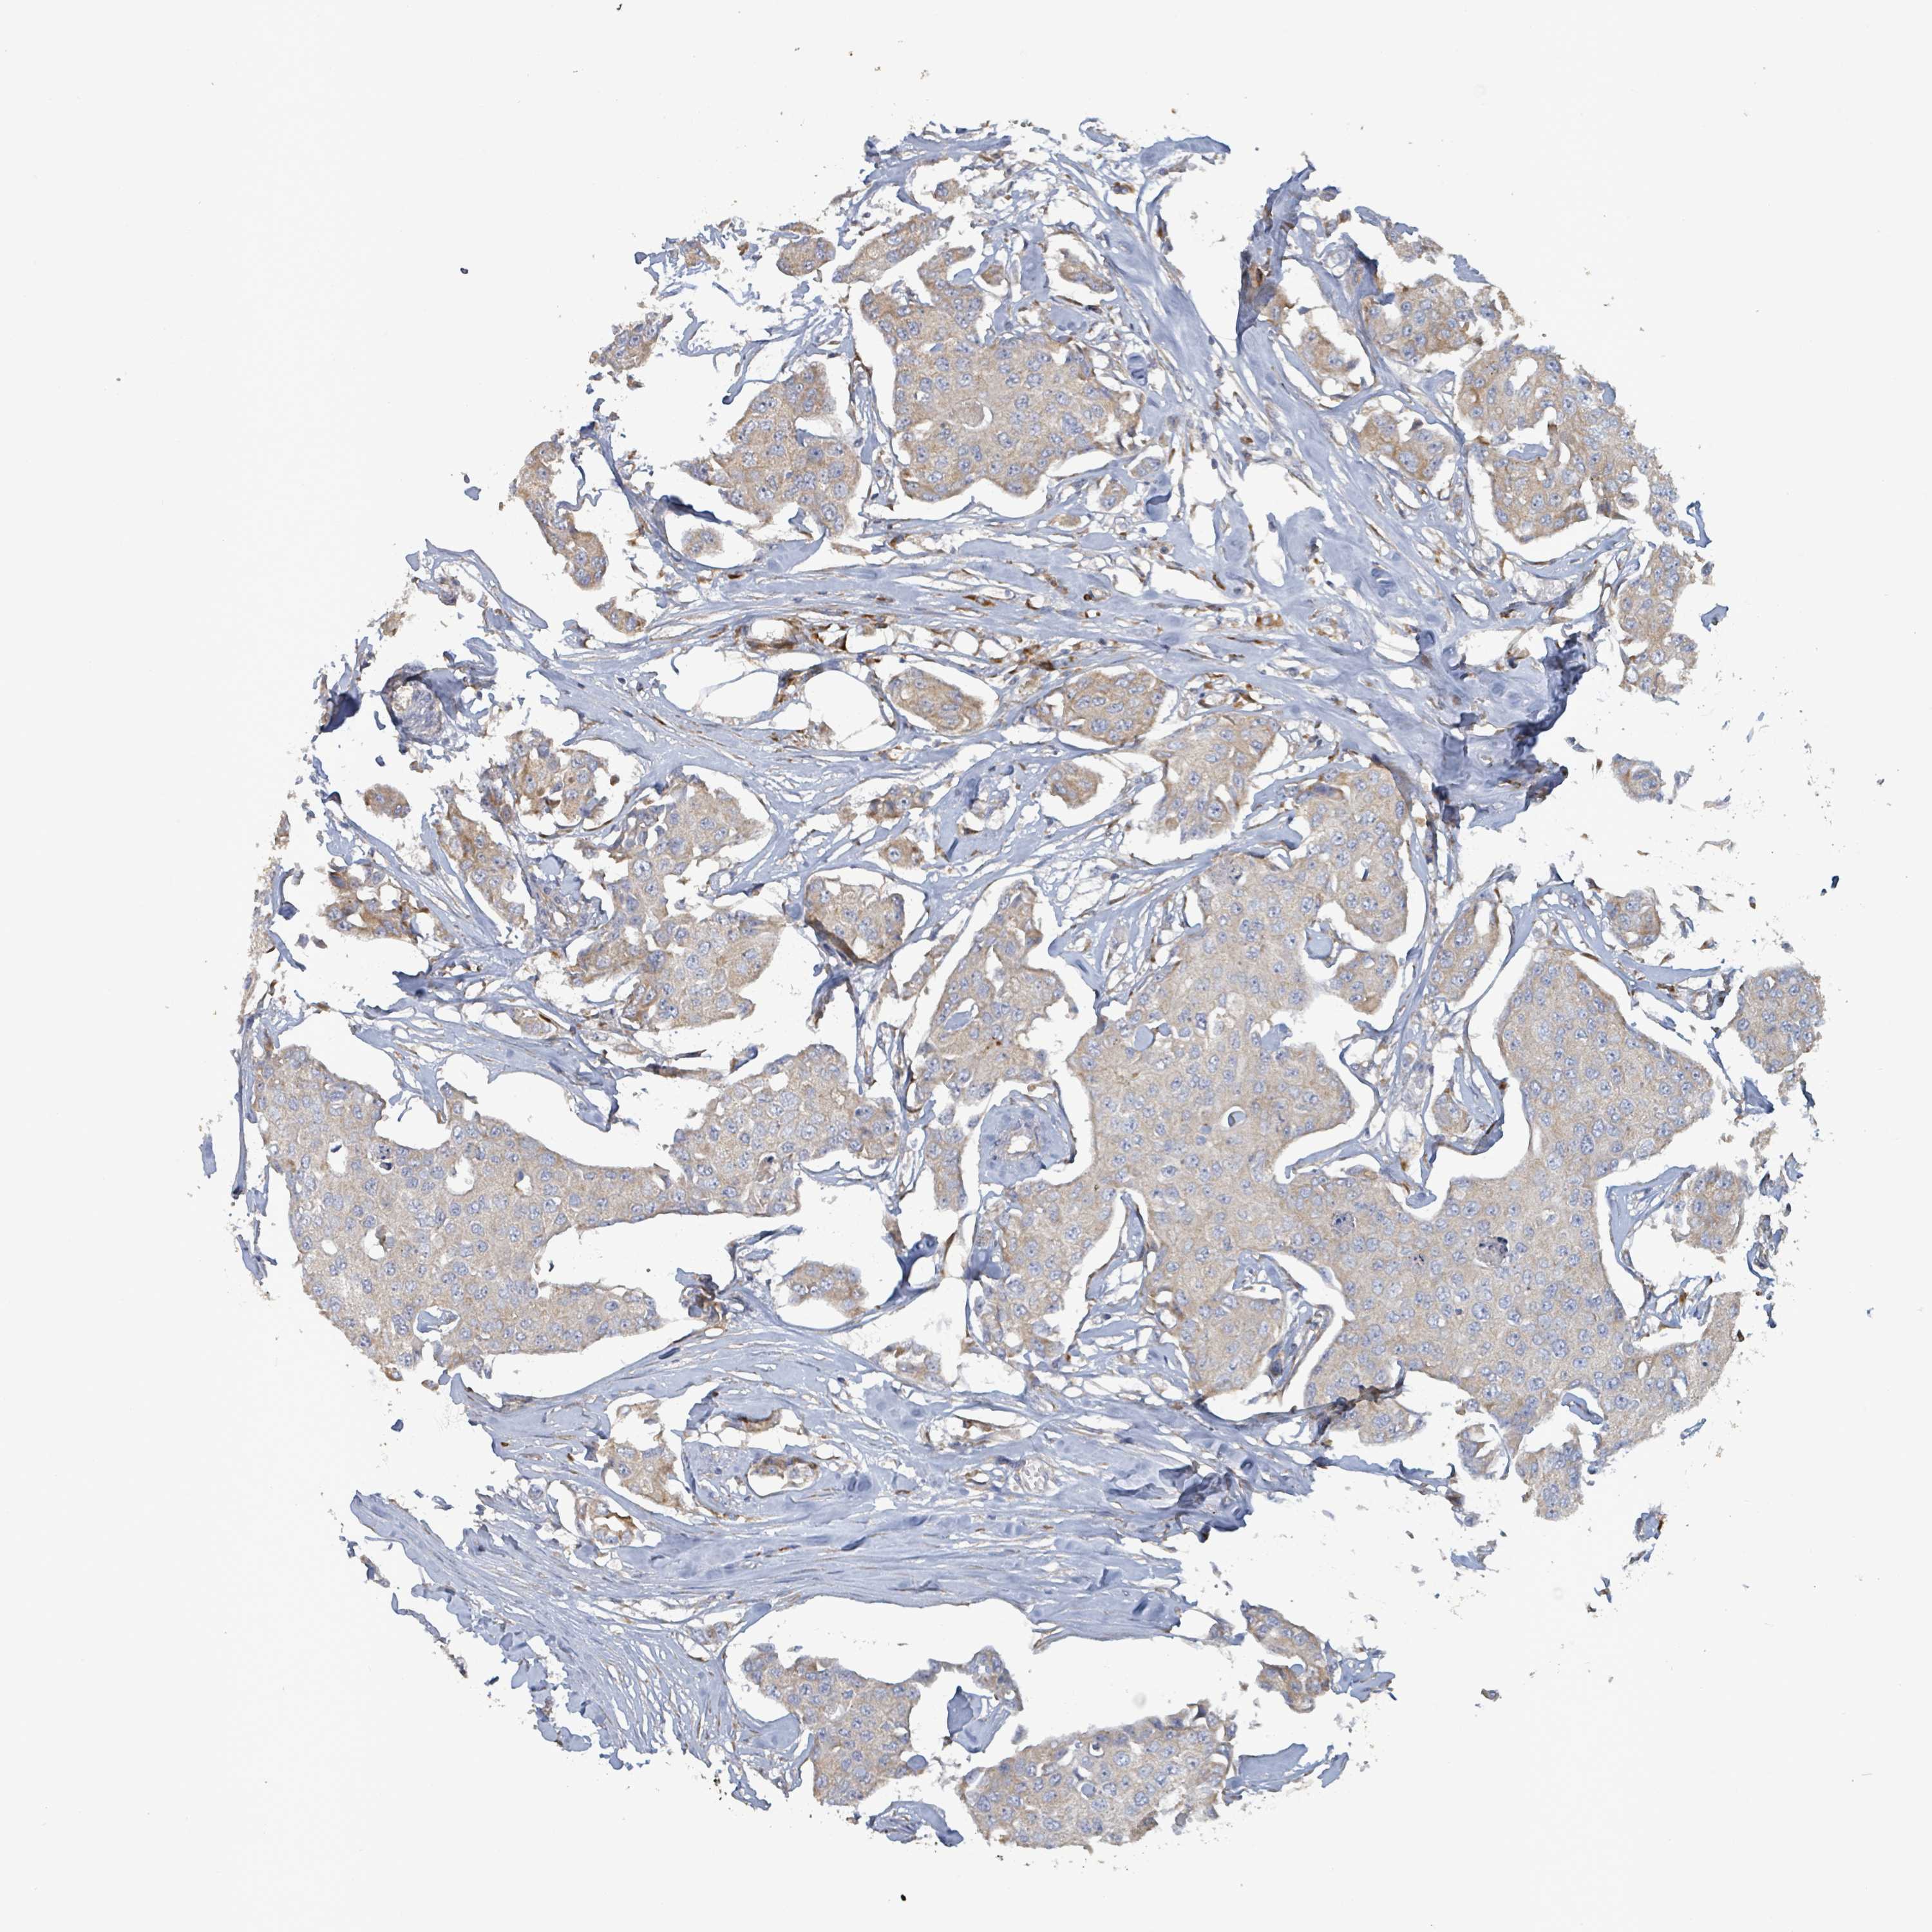

BRCA TCGA BRCA VALIDATION PROTEIN EXPRESSION